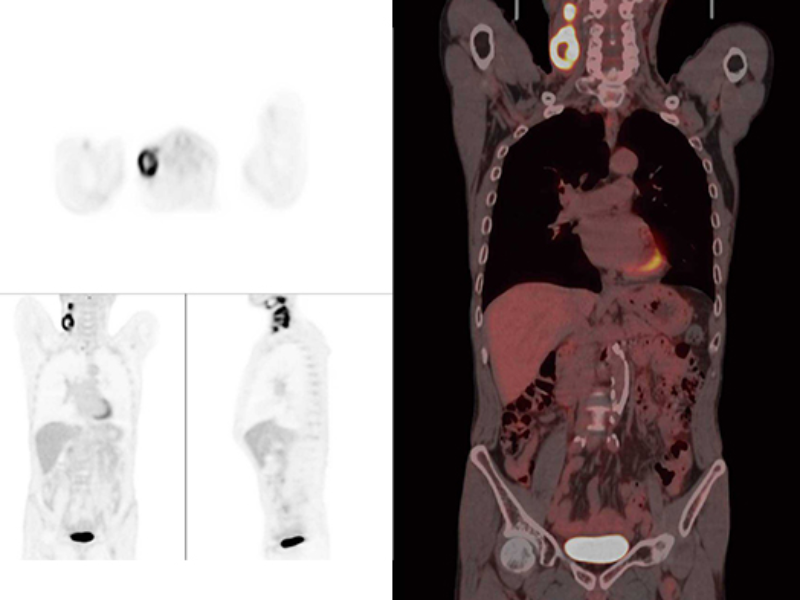

Fast Total-Body PET